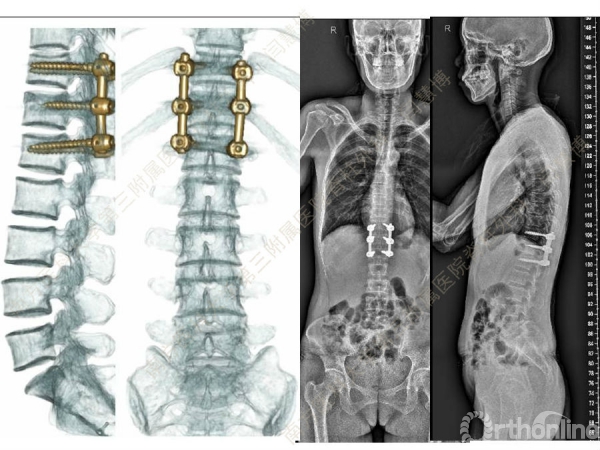

胸腰椎骨折是指由于外力造成胸腰椎骨质连续性的破坏,在如车祸、高处坠落等意外事故中,是最常见的脊柱损伤。老年患者由于本身存在骨质疏松,甚至有可能因为一些如滑倒、跌倒等低暴力因素导致胸腰椎骨折。胸腰椎骨折患者常合并神经功能损伤,且由于致伤因素基本为高能损伤,常合并其他脏器损伤,这为治疗带来了极大的困难和挑战。针对胸腰椎骨折,南方医科大学第三附属医院闫慧博教授介绍了他们运用微创方法治疗的经验。